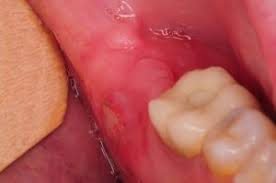

At each teething period, the gum will split to make part of the eighth tooth appear, which causes the gum to swell and become extremely painful. Most people fully recover from wisdom teeth surgery in three to four days. For a simple tooth extraction, pain can last between one and three days. Anywhere from a couple of days to a couple of weeks. How long does swelling last after wisdom teeth removal? It usually takes one week to remove stitches; The hole is the space that was previously filled by the tooth roots. After two weeks, all bruising should fade, and you should be feeling back to normal.

Having wisdom teeth removed creates a hole or opening that we call a socket. In an ideal situation, swelling should improve after a few days. The hole is the space that was previously filled by the tooth roots. Read on for why wisdom teeth may cause jaw pain and how you can get relief. In case you have been through extensive procedures, it might take an additional couple of days.